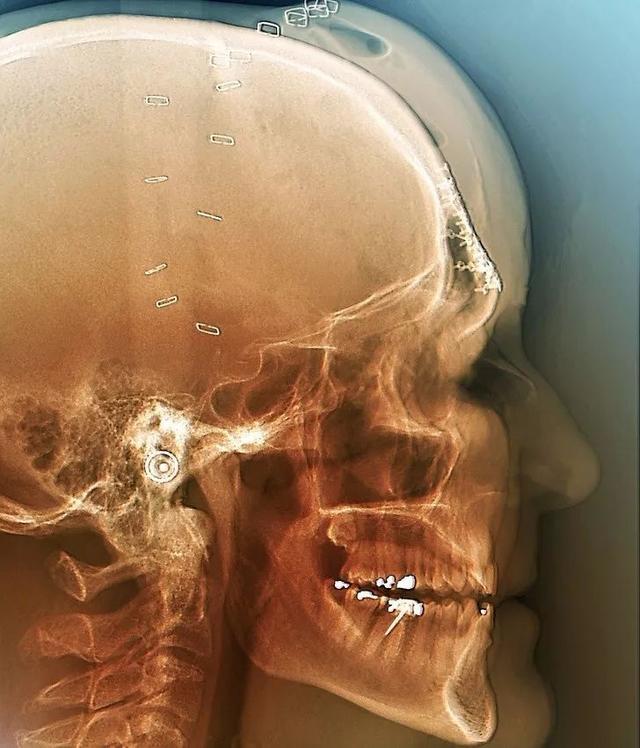

受伤的头骨在手术后的透视图